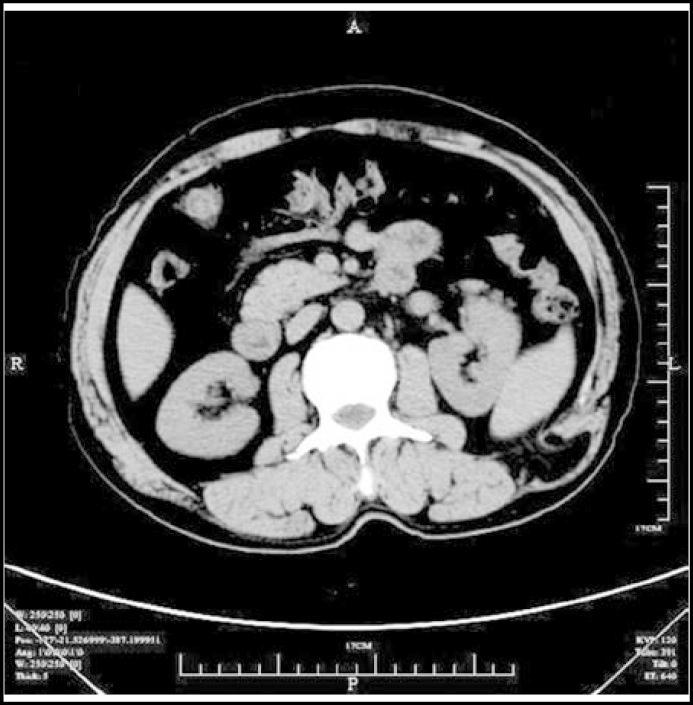

Lumbar hernias are very rare posterolateral abdominal wall hernias, and they are spontaneous in most adult patients. Here we report two cases of spontaneous lumbar hernias associated with chronic obstructive pulmonary disease (COPD). Some factors such as chronic cough, poor nutritional status and old age in patients with COPD would contribute to lumbar hernia.

https://cdn.ncbi.nlm.nih.gov/pmc/blobs/341c/3809316/fc09e0a92895/pjms-29-874-g001.jpg